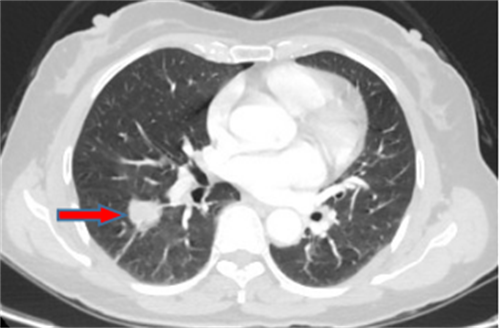

郭女士,63岁,体检发现右下肺结节20天,术后病理诊断肺结节为浸润性腺癌。